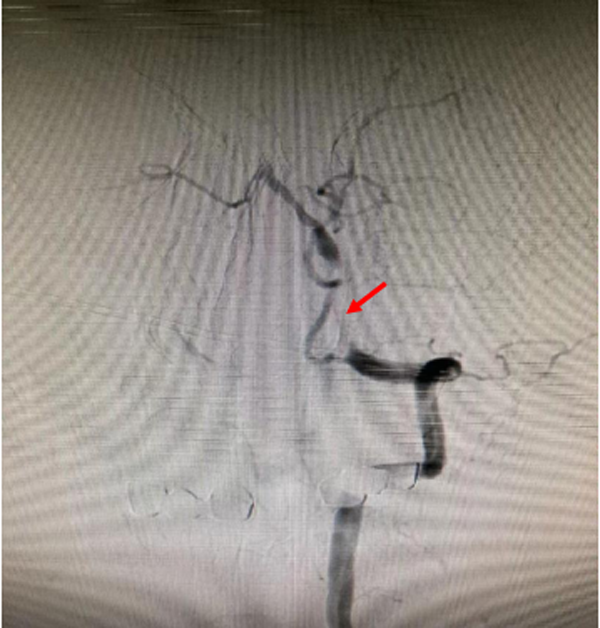

左侧椎动脉发出小脑后下动脉后以远闭塞

微导管穿越狭窄闭塞处后与导引导管同时造影确定病变具体长度